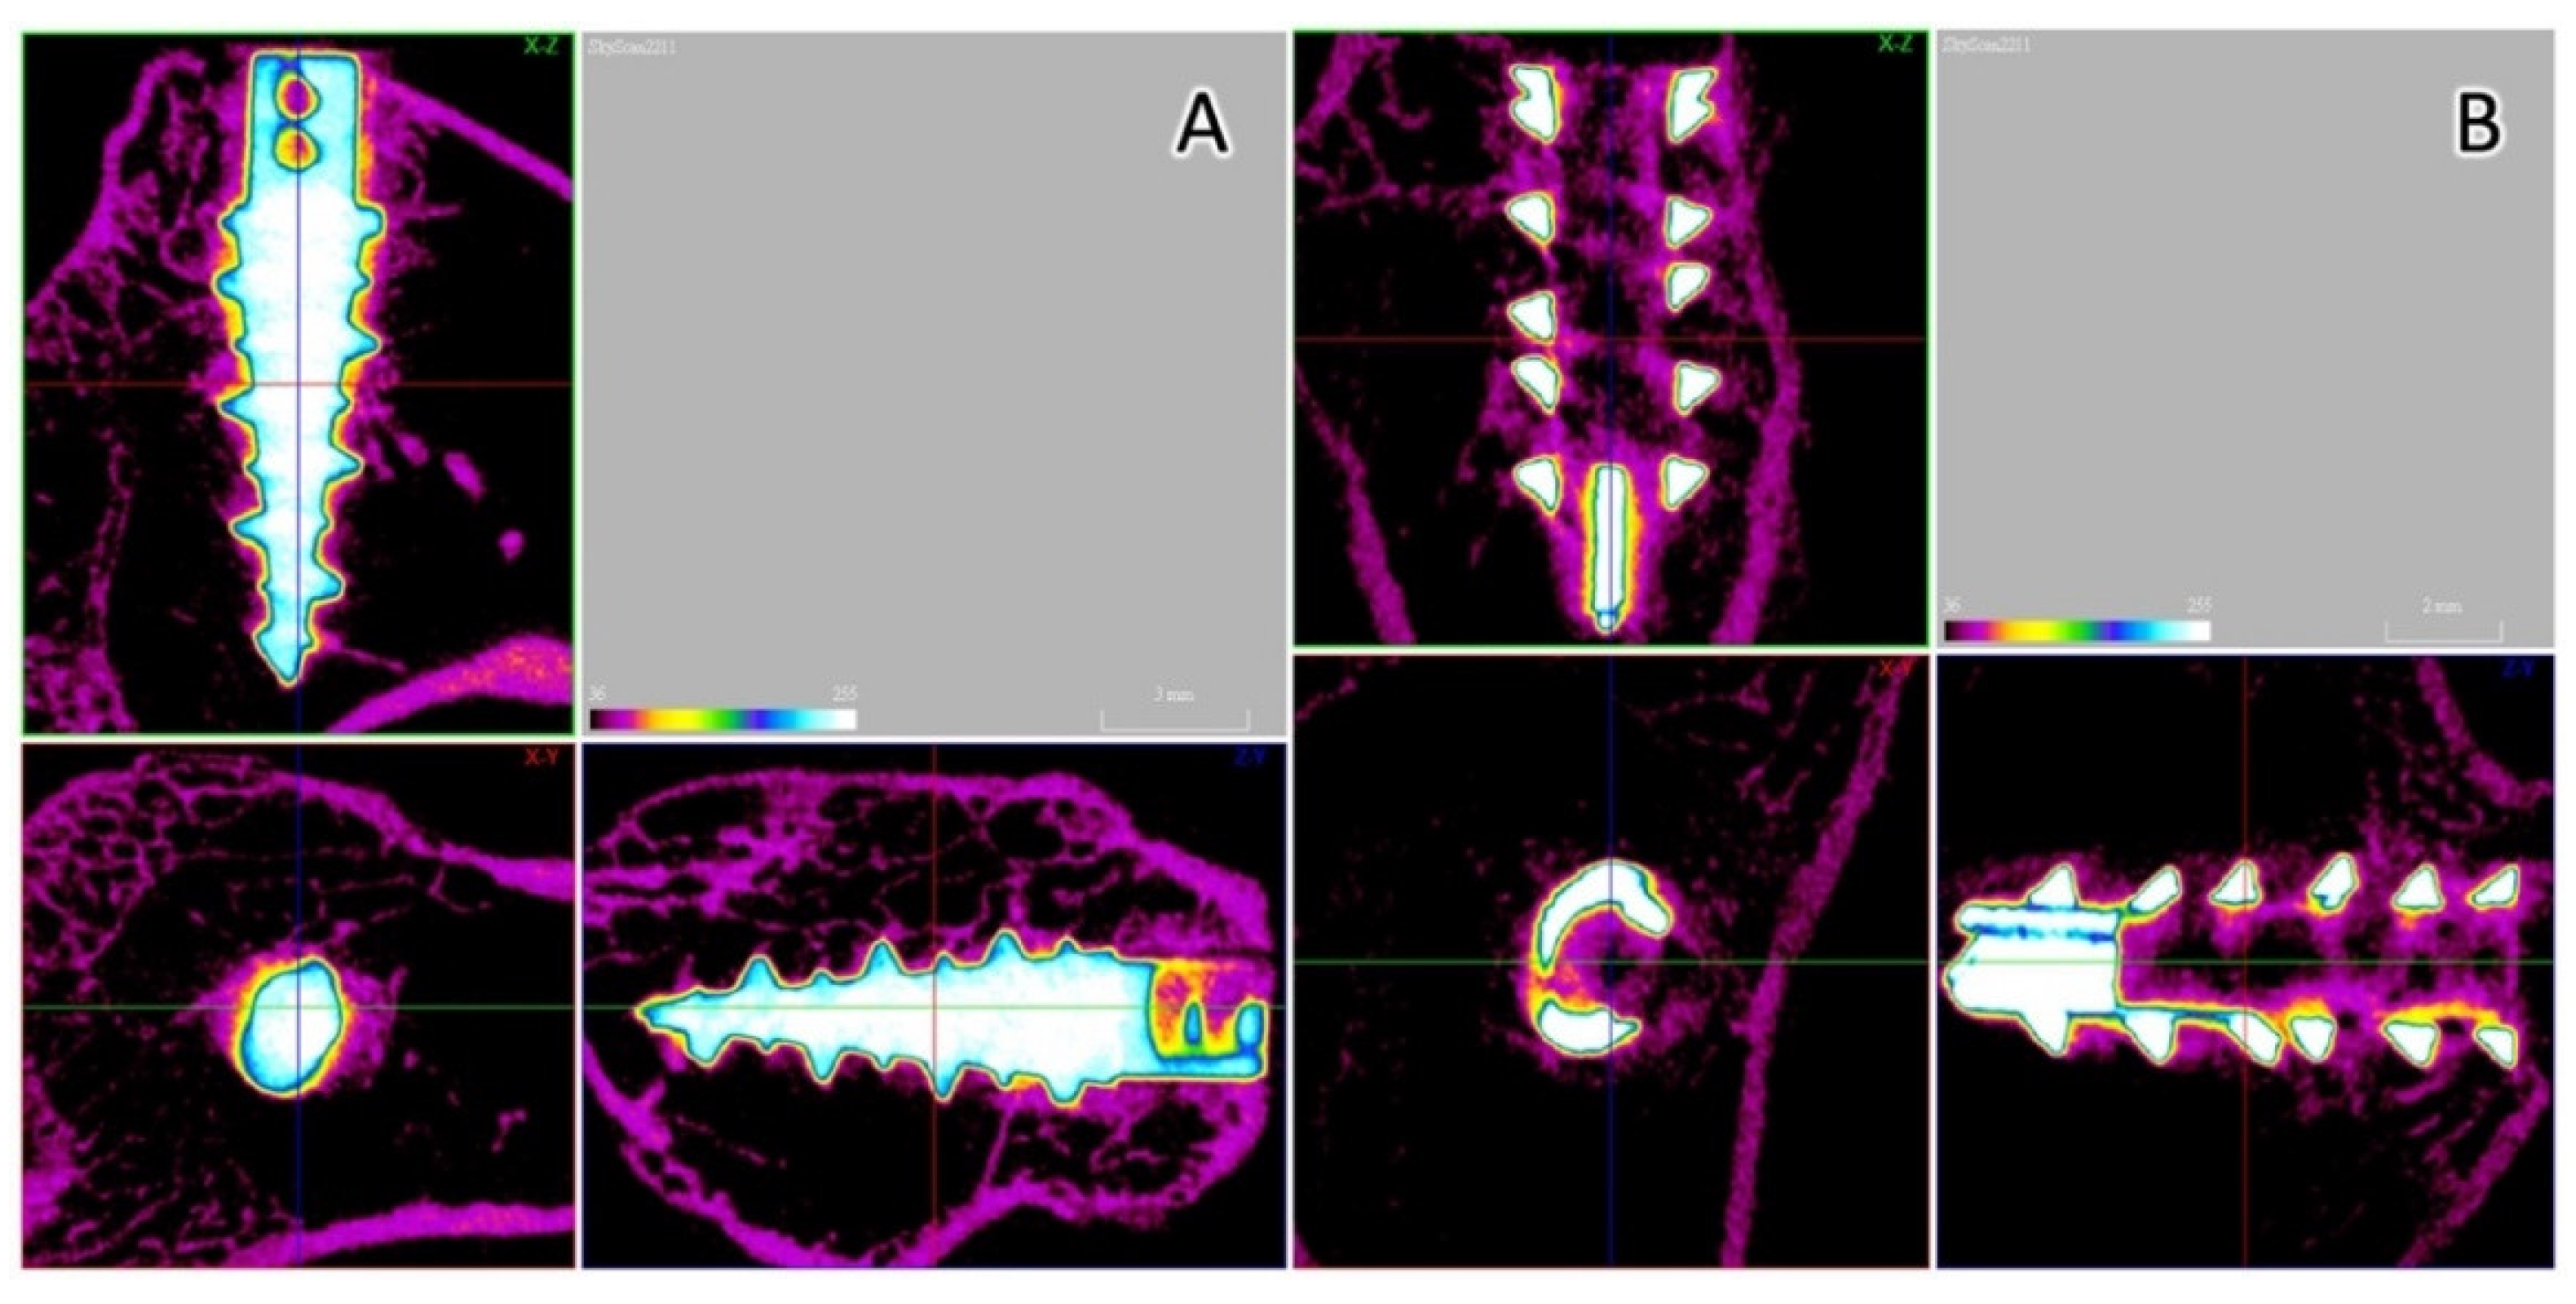

2.5. Micro-CT Analysis

3.5. Micro-CT Analysis

3.6. Histological Analyses